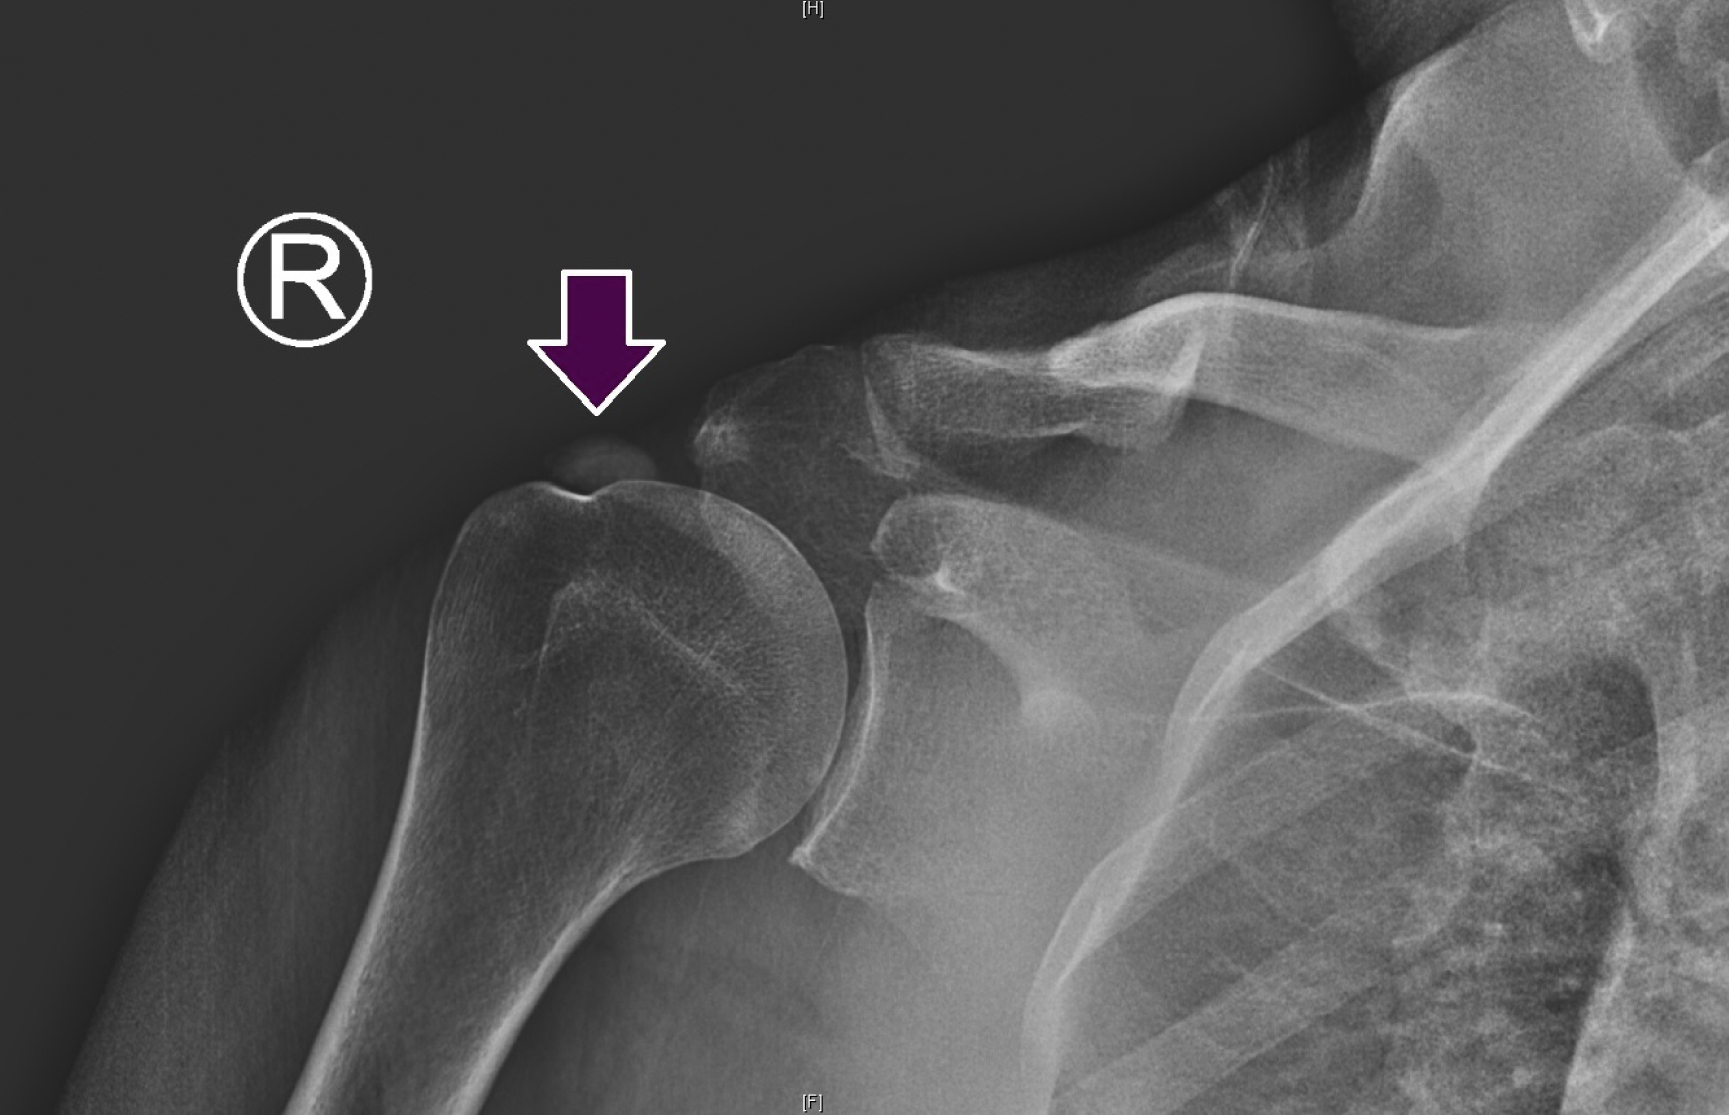

Calcific tendinopathy is an acutely or chronically painful condition associated with the deposition of calcium crystals in or around tendons. Although it can impact any tendon, the condition appears to be more prevalent in the rotator cuff. The underlying cause is still debated though has been attributed to tissue hypoxia and degeneration due to overuse. More common in females, studies have shown an association with diabetes mellitus, thyroid disorders, and nephrolithiasis along with a potential genetic predisposition. While it can affect any of the rotator cuff tendons, it seems to have a predilection for the supraspinatus, up to 80% of the time. The symptoms are similar to those of an impingement syndrome and the condition generally affects individuals between the ages of 30 and 60 years. Calcium deposition occurs over time and then undergoes spontaneous resorption. This resorptive phase is thought to contribute to the observed pain, though the severity of the symptoms is not correlated with the size of the deposit. Pain is believed to be in response to the local chemical pathologic disorder or direct mechanical irritation. On physical examination, there may be specific tenderness over the greater tuberosity as well as symptoms consistent with impingement. Plain film radiographs may show calcification in or around the rotator cuff tendons ( Fig. 103.5 ). The presence of calcium in the tendon does not necessarily confirm the origin of the pain because asymptomatic patients may demonstrate evidence of calcification on a routine radiograph. Ultrasound has proven useful in both the diagnosis and treatment (i.e., percutaneous needle lavage) of calcific tendinopathy.

Plain films of the right shoulder revealing a prominent calcium deposit in the supraspinatus tendon resulting in acute pain and decreased range of motion secondary to calcific tendinopathy.